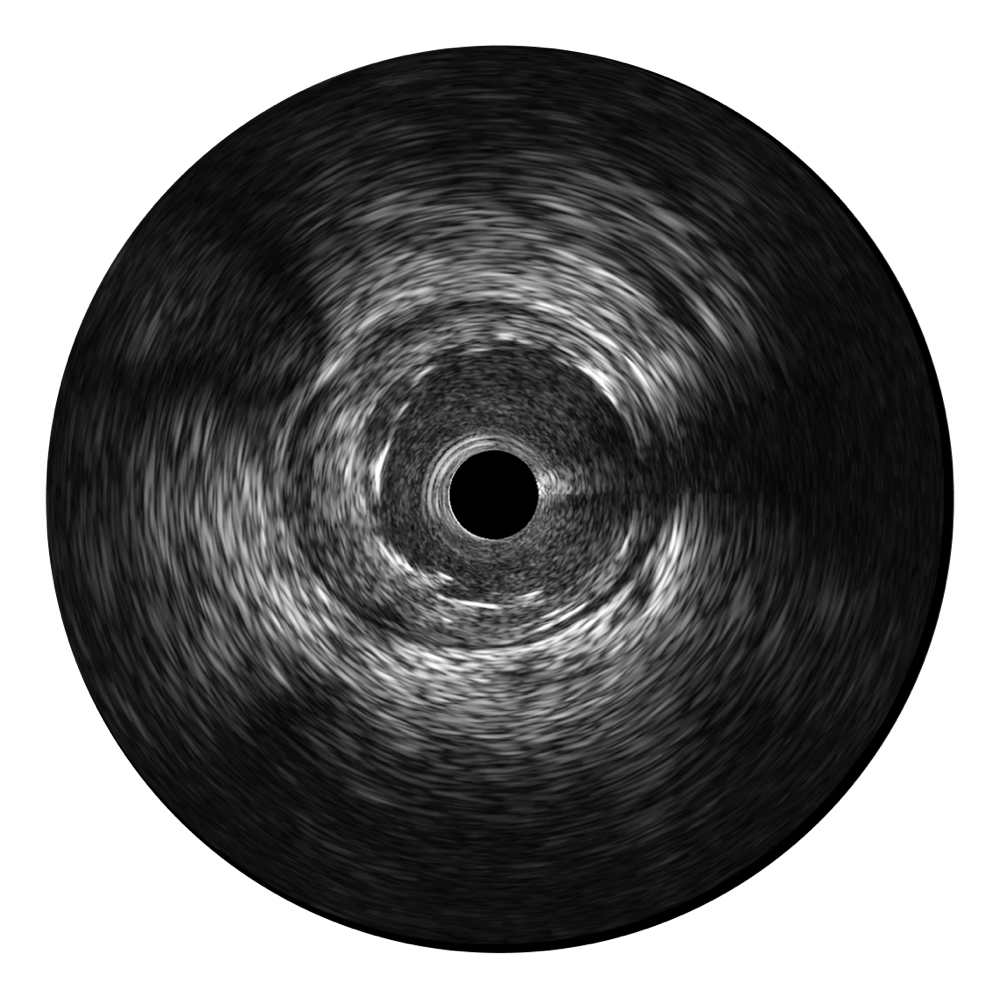

传统IVUS图像

对比传统IVUS导管成像,诸侯快讯官网宽频IVUS图像的近场支架梁显影更细腻,远场中膜外血管仍清晰可辨,兼顾远中近,兼顾分辨力与穿透深度